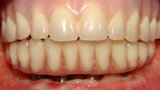

Fig. 5. Prótesis Híbrida inmediata y radiografía control con 6 años post-operatorio